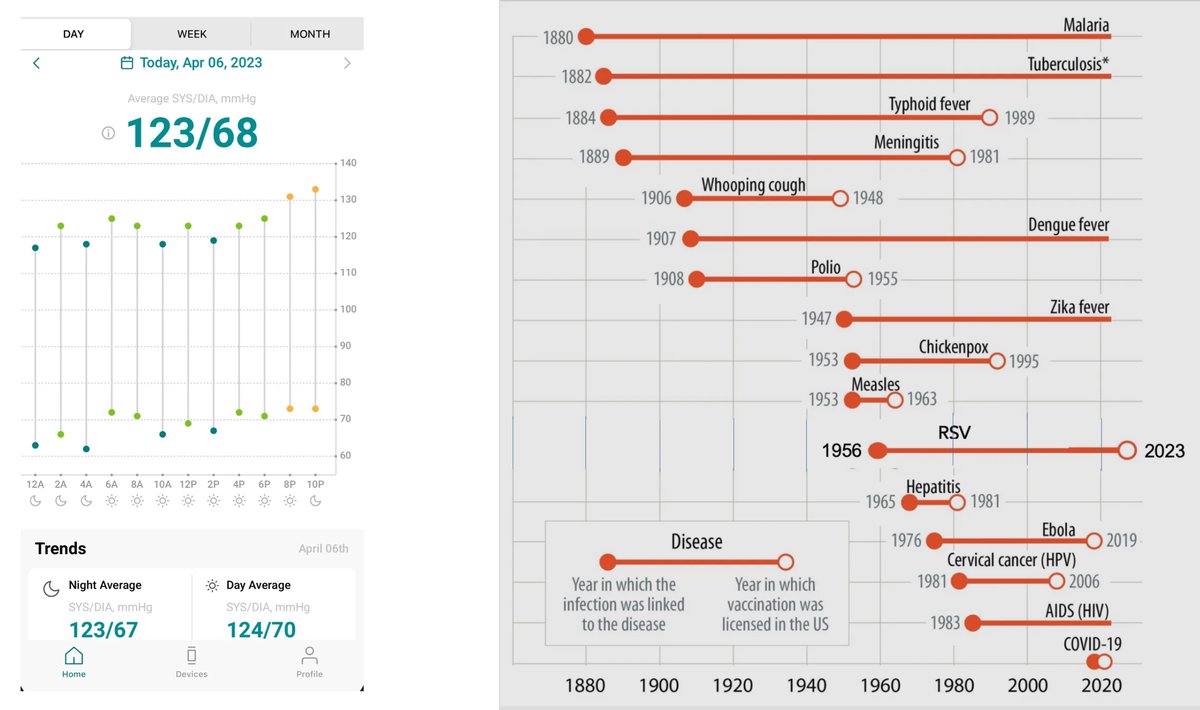

Great #AHA23 so far: AHA Research 🥸8 Trials: 8 take aways below Read the read👇👇 1/ATRESIA: Patients with subclinical atrial fibrillation can benefit from apixaban to reduce the risk of stroke and systemic thromboembolism.